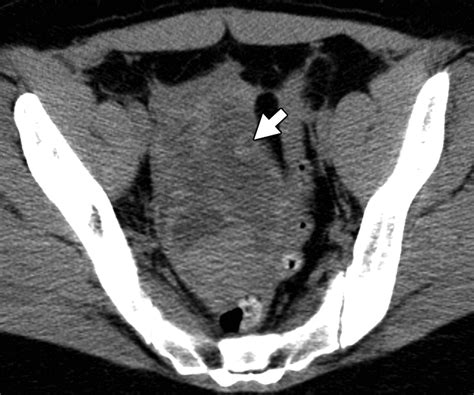

Computed Tomography (CT)

CT scans can also be used to evaluate the pelvic structures, including the Ovarian Suspensory Ligament. CT is particularly useful in emergency settings, where quick imaging is necessary to diagnose conditions such as ovarian torsion or rupture. However, CT scans involve radiation exposure, so they are typically used when other imaging modalities are not available or contraindicated.